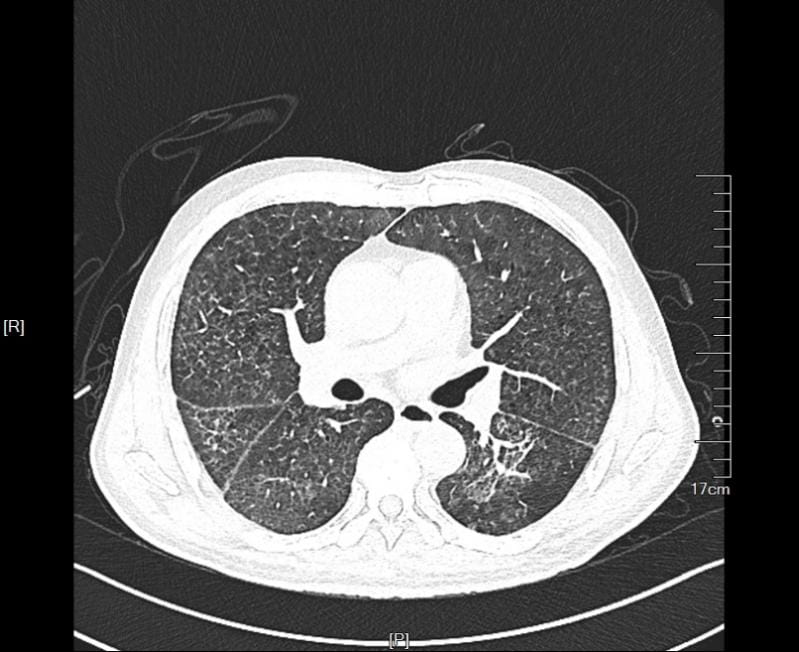

▲术后CT